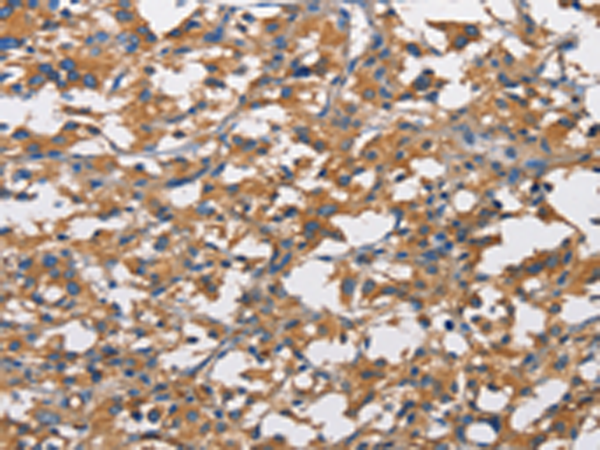

分类: 科研抗体货号: P08010别名: ZFYVE11; FYVE-DSP2应用: IHC反应种属: Human, Mouse